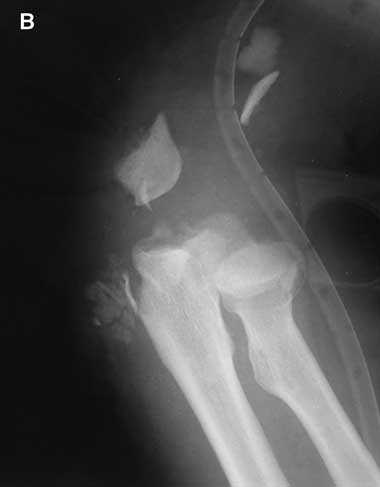

The most severe upper-arm injury involved Patient 7, with loss of the right distal humerus and olecranon, combined with an ulna nerve injury (Box 3). Initial treatment consisted of debridement and application of a bridging external fixator across the lost elbow joint (Box 4). This was complicated by iatrogenic radial nerve neuropraxia caused by the insertion of a Steinman pin. The external fixator was later replaced by a humeral allogeneic bone graft, an elbow prosthesis, and plate fixation of the humeral shaft (Box 5). The same patient also subsequently underwent a revision of the humeral plate procedure after a deep infection with Staphylococcus epidermidis was identified.